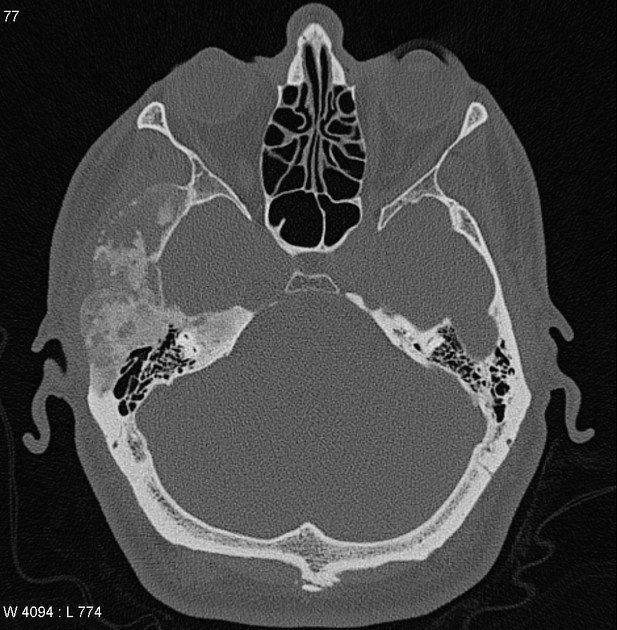

শিশুদের ক্যান্সার